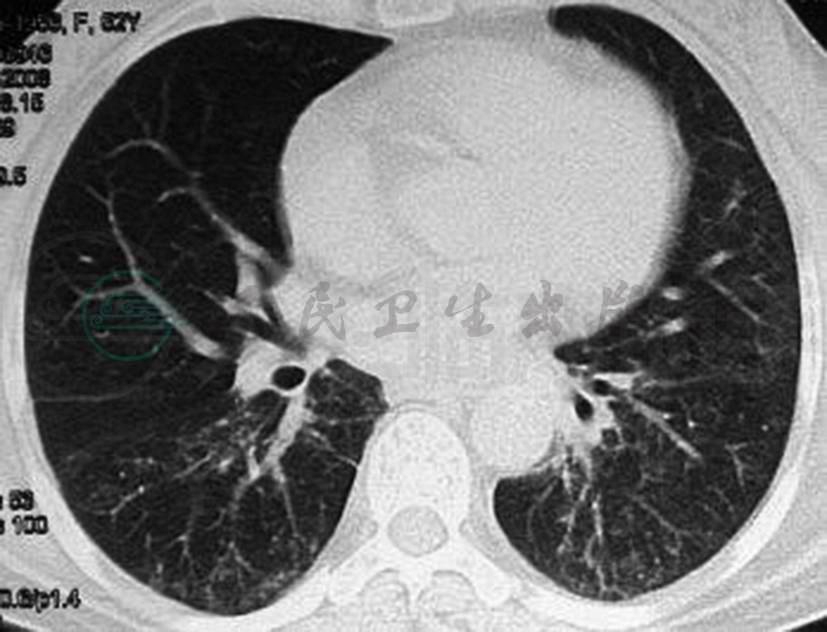

患者,女性,51岁,因“气促2个月,发热1个月,咳嗽、咳痰1周”于2008年2月15日入院。患者2个月前受凉后出现咽痛,无畏寒发热、咳嗽、咳痰等不适,自服感冒药后稍缓解,4天后感气促,活动后加重,在当地多家医院及诊所间断对症治疗,气促加重,遂于2008年1月5日至1月13日在当地市中心医院住院治疗。在住院期间出现下午发热,体温最高达37.5℃,查肺部CT(图1)示双肺多发渗出病变,先后予“头孢他啶,依诺沙星”,“头孢噻肟,克林霉素,氨曲南,亚胺培南”抗感染,患者症状逐渐加重。于1月13日转入某教学医院住院治疗,查血白细胞、血沉升高,动脉血气分析示Ⅰ型呼吸衰竭,诊断考虑:社区获得性肺炎、肺结核待查,入院后予“阿奇霉素,帕珠沙星”抗感染,并予“异烟肼,利福平,吡嗪酰胺,乙胺丁醇”抗结核治疗。治疗1周后复查肺部CT示病变无明显好转,考虑“病毒性肺炎”,遂停抗结核治疗,加用“病毒唑(利巴韦林)”抗病毒,“甲泼尼松”抗炎,无创辅助呼吸机辅助呼吸。患者发热好转,但仍感活动后气促。并于2月5日改用“替考拉宁”抗感染,“氟康唑”抗真菌治疗,症状仍无好转。1周前出现咳嗽、咳痰,咳白色黏稠痰,遂转入我院我科治疗。患者起病以来体重下降约5kg。既往史、个人史无特殊。

图1 肺CT(2008-01-09)